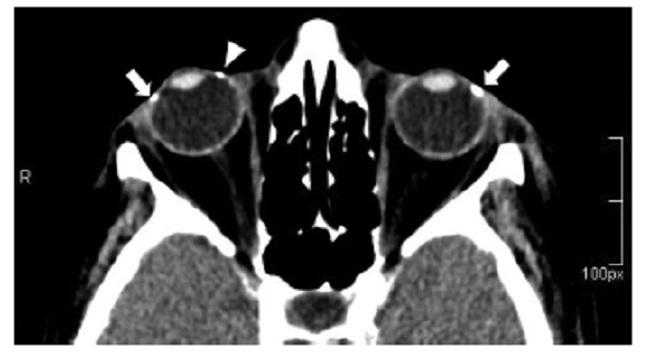

Las calcificaciones oculares y el material médico se pueden confundir con cuerpos extraños u otras lesiones orbitarias1. Las localizaciones típicas de las calcificaciones permiten diferenciarlas de cuerpos extraños hiperdensos. Las más frecuentes son las calcificaciones trocleares, las placas esclerales, las drusas del nervio óptico y la ptisis bulbi. Las primeras tienen localización superomedial dentro de la órbita (Fig. 13), en la tróclea del músculo oblicuo superior, aunque se pueden observar en todas las edades, hay mayor prevalencia de calcificaciones trocleares en pacientes con enfermedades autoinmunes y niveles elevados de fosfatasas alcalinas. Las placas esclerales se localizan en los sitios de inserción de los músculos rectos medial y lateral (Fig. 14) y son más comunes en los pacientes ancianos. Las calcificaciones que ocurren cerca del disco óptico se conocen como drusas del nervio óptico (Fig. 15), las cuales se asocian a degeneración macular y pueden ser causa de pseudopapiledema benigno. La ptisis bulbi es una atrofia y calcificación del globo ocular como secuela de enfermedades infecciosas, inflamatorias o traumáticas previas (Fig. 16) (1,11. Los imitadores de lesiones abiertas del globo ocular incluyen las deformidades como coloboma, estafiloma y el globo ocular elongado por glaucoma o miopía (Fig. 17). Las masas orbitarias y los hematomas también pueden alterar el contorno del globo ocular y asociarse a calcificaciones o relacionarse con desprendimiento de retina (Fig. 18) (1,6,8,11.